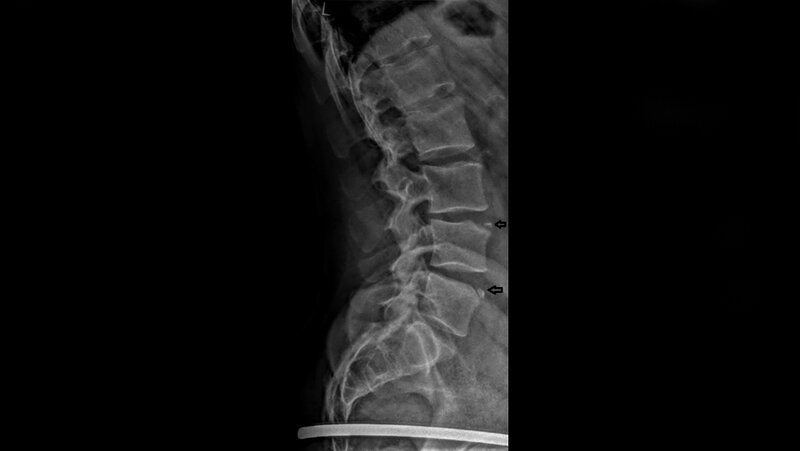

Die persistierende Wirbelkörperrandleiste ist eine mögliche Läsion der Wirbelendplatten. Sie stellt eine Normvariante dar. Neben Diskusdegenerationen tritt sie gehäuft bei Athleten auf.

Anterior limbus vertebrae (ALV) is one kind of endplate lesion. It is a variant of regular development. Athletes have a high prevalence of disk degeneration and ALV.